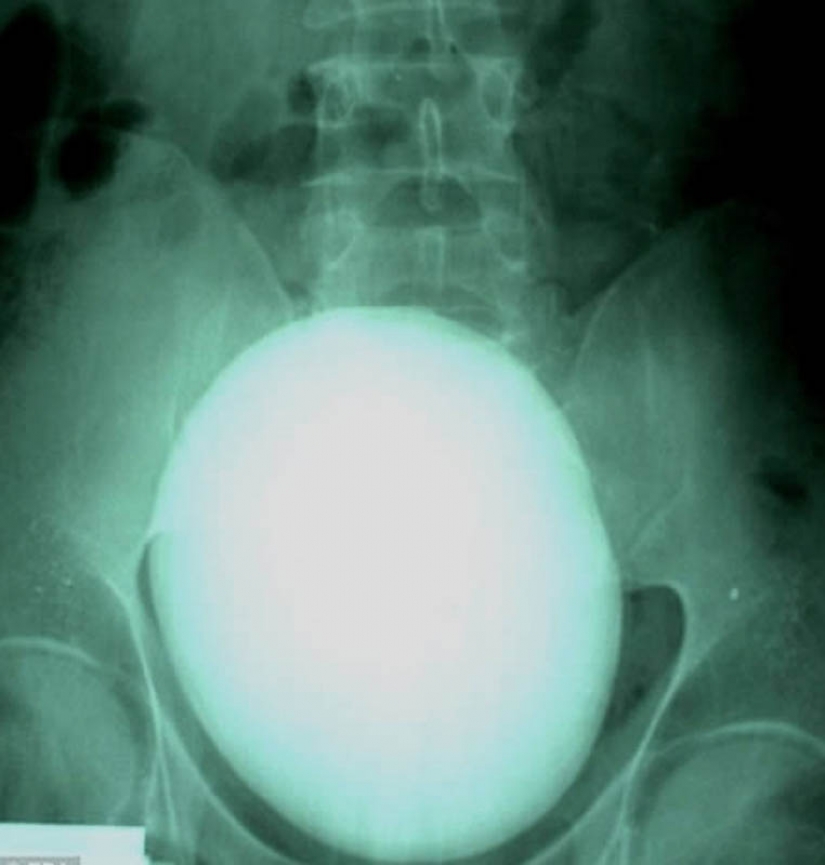

17. Here is such a 15-cm kidney stone weighing 1.1 kg was removed the patient from Hungary.